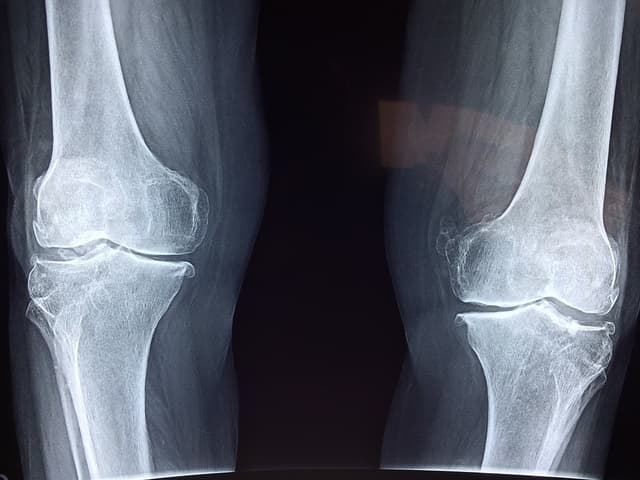

Leg: When bones become weak, they can start to bend, which can cause the individual to become bow-legged. Misshapen or enlarged bones in the legs can create added stress in nearby joints, which can lead to osteoarthritis in the hip or knee.